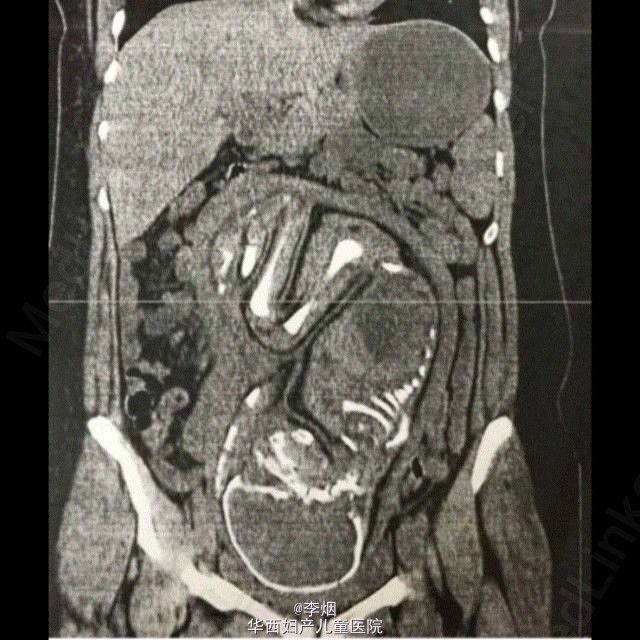

谁能看出这个CT图有什么异常?